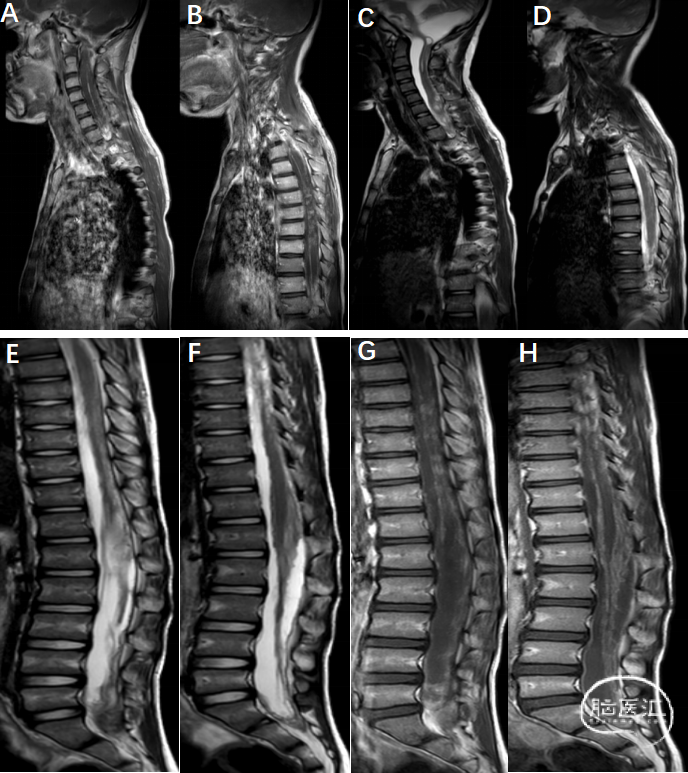

术后复查

2025-12-21:

A-D:颈胸段脊髓多发囊变较术前减少,但软脊膜仍增厚并明显强化,增强后颈胸段椎管内多发结节状强化,颈髓受压后移。

F-H:马尾终丝表面脊髓明显增厚伴强化,较术前相似。